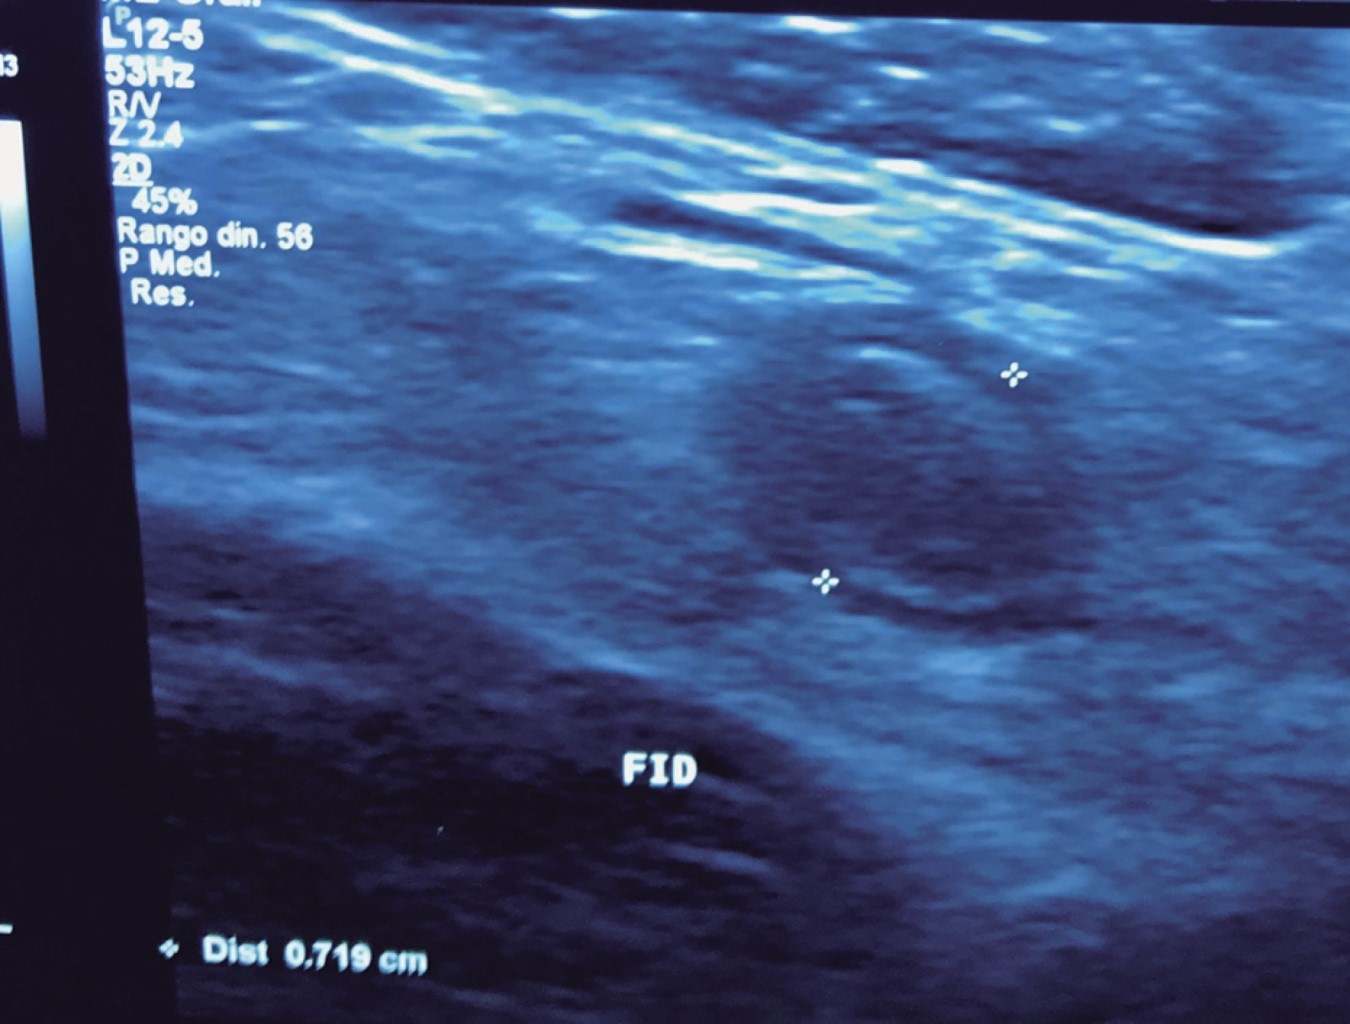

The general surgeon deals with clinical problems involving the digestive tract, the neck, the abdominal wall, and disorders of the circulatory system and the thorax. A paper published in 2008 by Lindelius,15 demonstrated that the implementation of ultrasound by the general surgeon in cases of acute abdominal pain increased diagnostic accuracy by 7.9%. In the daily consultation of the specialty, incorporating sonographic scanning to the explored area adds minutes to the clinical examination that provides data of notable value due to its objectivity and precision. The abdomen is usually the site most frequently explored by general surgeons. It is possible in a daily consultation to do the entire upper abdominal ultrasound protocol in minutes, which includes both upper quadrants and the flanks, being able to observe the liver, gallbladder and bile ducts, both kidneys, the spleen, part of the pancreas and, with the help of color Doppler, the main vessels of the region such as the inferior vena cava, abdominal aorta, portal vein, splenic vessels, and the hepatic artery. There may be limiting factors such as gastric contents, the filling level of the gallbladder, or the patient's constitution and ability to cooperate with the study. However, with daily practice, sufficient skills and refinement are acquired to achieve, with accumulated experience, images of immediate diagnostic relevance. In the training phase, contrasting our findings with information available on the web, with imaging colleagues, or surgeons already experienced in ultrasound, will allow the essential feedback and mentoring of any learning curve. Traditionally, it was considered that those organs containing a mixture of liquid and gas (intestine, stomach) are not assessable by ultrasound; the gas produces a rarefaction effect, as it does not compress the waves as a solid tissue or a liquid medium, the signals are then scattered preventing them from returning as echoes and allowing the processor to form an image congruent with the scanned organ. However, when this condition changes due to a pathological state, it is possible to identify the intestinal or gastric contents and give us a more approximate idea of what is happening in that abdomen. We can, for example, tell whether a stomach is full of liquid or whether the intestine contains solid, liquid, or gaseous residue. Today's equipment can even see the intestinal wall in detail when it is dilated. It can be distinguished when the colon is fluid-occupied at the level of the left flank as might be in amebic colitis or intestinal occlusion,16 where dilatation of the small bowel ≥ 25 mm, abnormal peristalsis, the presence of free intraperitoneal fluid and edema of the bowel wall are seen (Figure 2). In cases of acute abdominal pain, ultrasound can immediately allow differential diagnoses, such as the finding of a pyelocaliceal dilatation due to nephrolithiasis (Figure 3) or an abdominal aortic aneurysm (Figure 4). A prospective study performed in Irvine, California,17 found that the diagnostic ability of the first contact physician performing ultrasound to detect cholelithiasis has a specificity of 87% and a sensitivity of 82%, while the ultrasonography test performed by an imaging physician had a sensitivity of 83% and a specificity of 86%. In other words, by saving the patient's time, the diagnosis of cholelithiasis is feasible by adding a few minutes to the initial physical examination. In cases of appendicitis, the diagnostic method considered the gold standard is computed tomography (CT). However, it has drawbacks, such as its availability, its cost, and the risk of radiation in children and pregnant patients. In such situations, especially in children, females, or thin patients, ultrasound is a powerful tool that complements the initial clinical examination. The advantages of ultrasound over CT are its ubiquity (it is already in the emergency room), low cost, absence of radiation, and differential diagnosis with gynecologic or genitourinary causes of pain. In appendicitis, the sensitivity and specificity of CT are 99.4% and 80.0%, respectively. For ultrasound, the diagnostic sensitivity is 83% and specificity is 90%. The rate of negative appendectomy is slightly higher in the CT group than in the ultrasound group, i.e., 7.1% (3/42) (CT) compared to 4.67% (5/107) (ultrasound). It should be emphasized that ultrasound is an operator-dependent technique. Experience and quality of the equipment play an important role.18 Appendicitis has several characteristic findings, such as an edematous wall and general thickening. A noncompressible non-peristaltic tubular structure measuring more than 6 mm in diameter in the right lower quadrant is taken for criteria of positivity (Figure 5).19-21

Figure 5